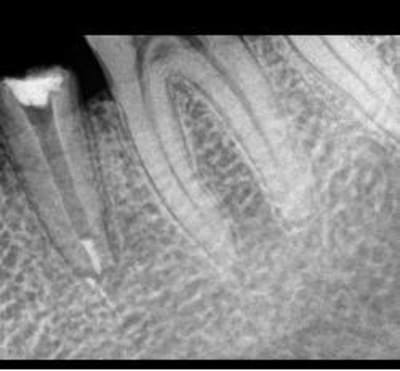

Une autre radio, après dépose...

A l'apex vous ne voyez pas comme l'apex avec fracture horizontal ? en meme temps je l'ai trop regardé cette radio, elle m'aveugle !

Mon patient vient de partir.

J'ai repris une radio.

Il a eu un peu mal durant la semaine mais moins.

Cependant, quand j'ai appuyé sur la racine, plus de douleurs vives, légère gene decrite par le patient.

Quand j'ai réintroduis l'inlay core, gène, douleur legère mais pas aussi brutale qu'avant.

Donc en faveur d'une desmodontite en passe de guerrir.

Cependant, du sang et meme un liquide purulent remonte du canal.

Quand j'ai passé un instrument, j'ai cherché la gutta pour voir mais je n'ai remonté que des petites boules de sang coagulée, un peu malodorante.

Mais pas de sensibilité du tout quand je passe linstrument (ct une lime 25)